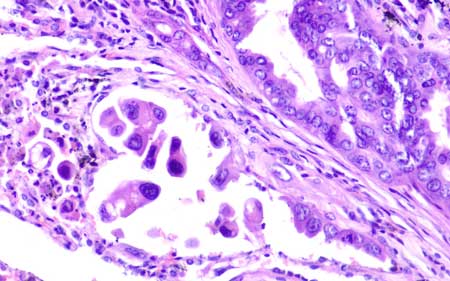

تکنولوژی پیشرفته و دقت بالا برای تشخیصهای قابل اعتماد. کیفیت تصویربرداری استاندارد جهانی برای نتایج دقیق. سیستمهای اسکن لام با رزولوشن بالا و قابلیت بزرگنمایی تا 100X برای مشاهده جزئیات دقیق بافتها.

Cancer Research